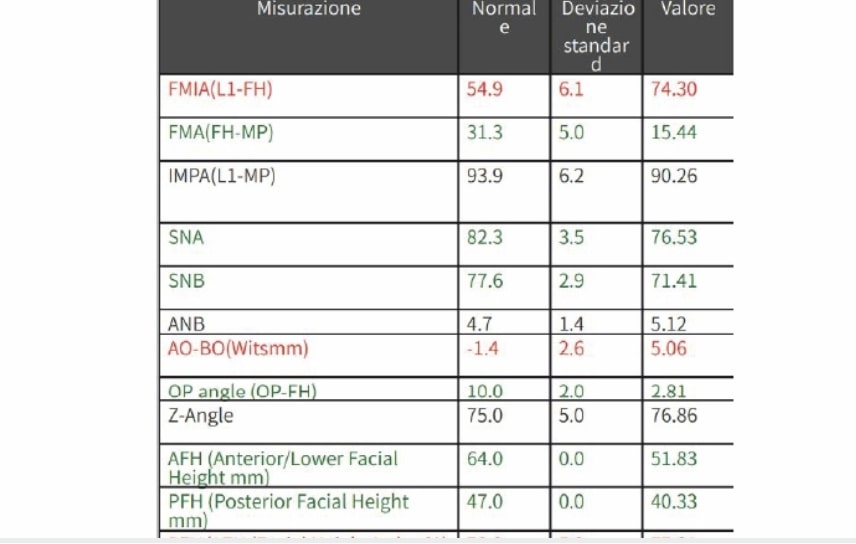

Clinical examination and diagnosis

FUNCTIONAL: Suction of the lower lip and Labial incompetence.

FACIAL: class 2 profile with Lower jaw deficit

SKELETAL PATERN: Class 2

DENTAL:

- Molar and Canine class 2 on the right side – Molar and Canine clss 1 on the left side

- Upper diastema (11-21)

- Increased Overjet

- DeepBite

- Reduced Transversal Diameters

- Deviated Lower Midline 2 mm to the Right